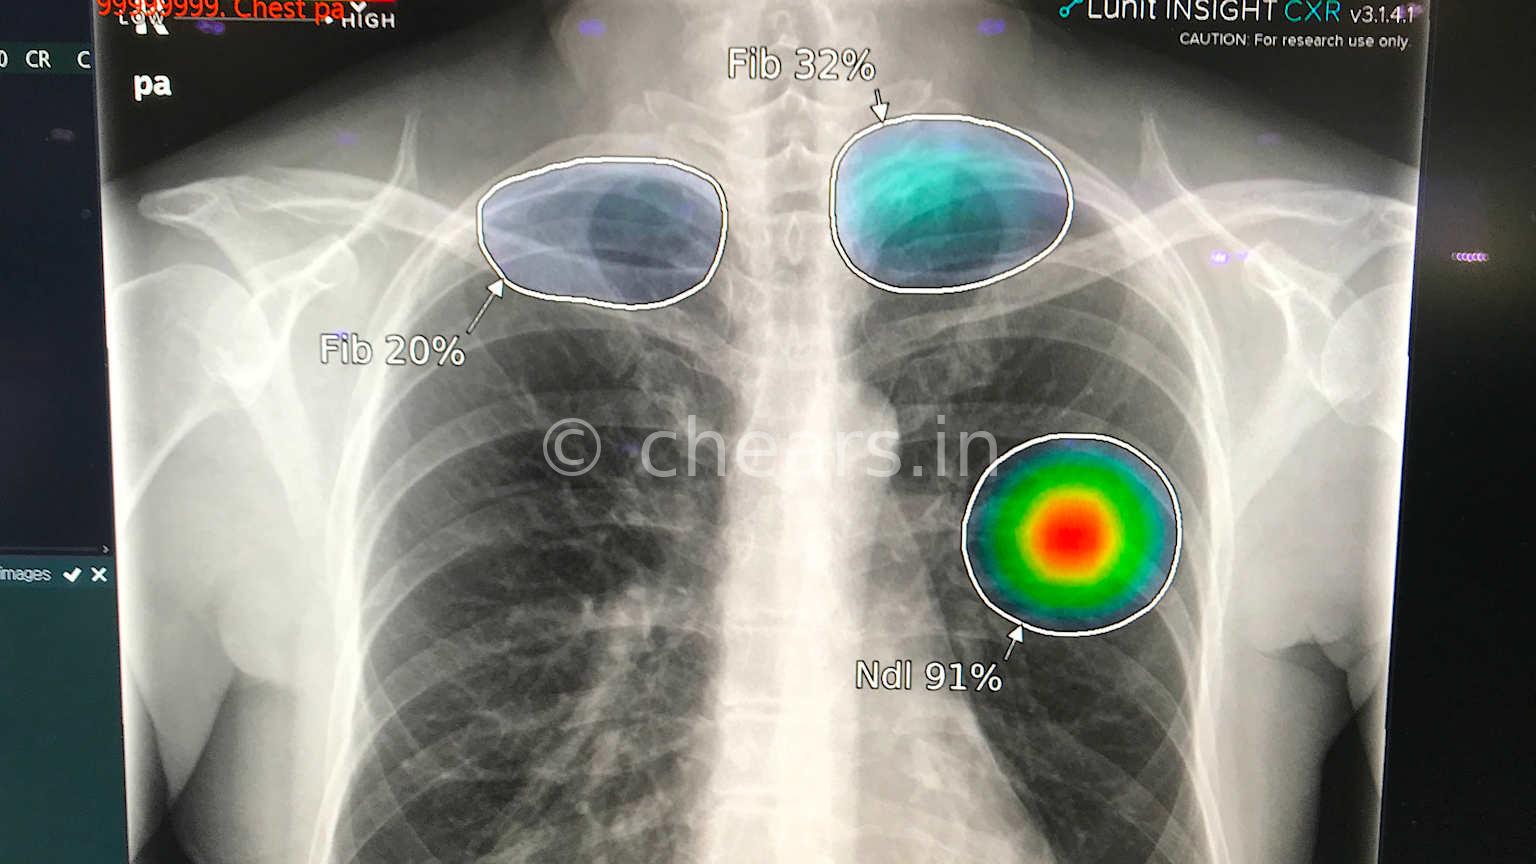

Medical imaging is the most mature and commercially advanced AI use case in healthcare. Deep learning models are now routinely used to support radiologists and other imaging specialists in detecting anomalies in X-rays, CT scans, MRI, ultrasound, and nuclear imaging.

AI algorithms have achieved high sensitivity and specificity in tasks such as lung nodule detection, breast cancer screening in mammography, intracranial hemorrhage detection, and retinal image analysis for diabetic retinopathy. The prevailing deployment pattern is "augmented intelligence" rather than fully autonomous AI: models serve as a second reader or triage tool, while final responsibility remains with the clinician.